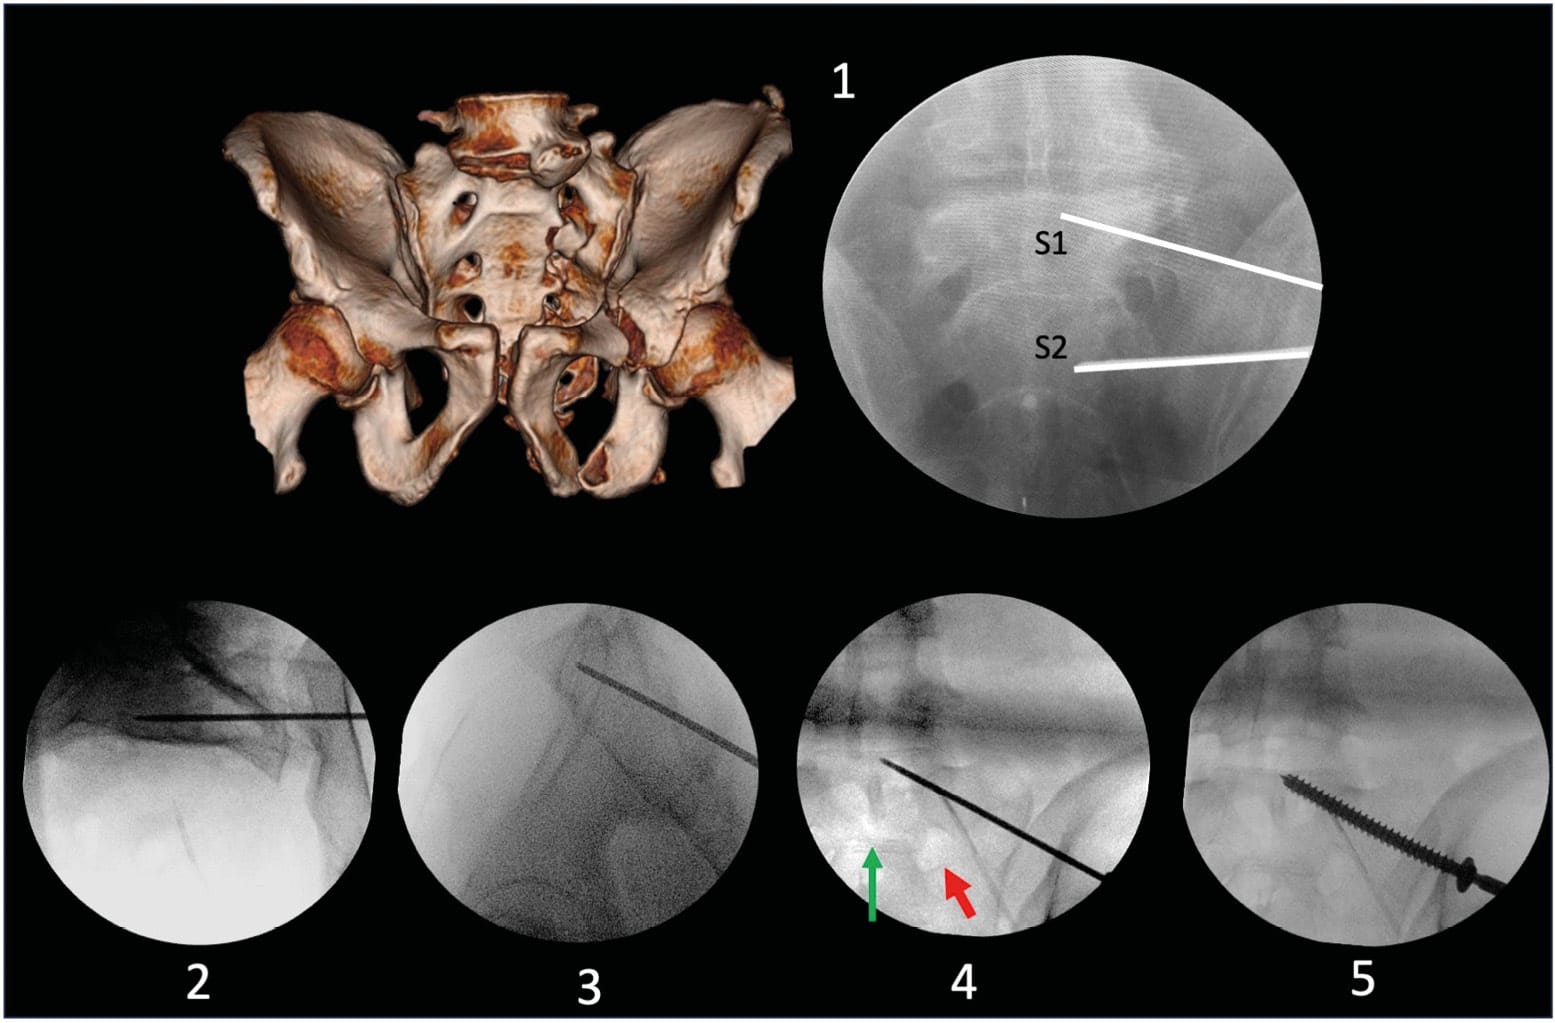

The lumbosacral junction is one of the most variable regions of the spine. Although the total number of vertebrae in the thoracolumbosacral region remains constant, sacral fusion levels differ. It is important to look for radiographic characteristics of dysmorphism, as this variation significantly alters the upper sacrum and therefore the screw corridors (Figure 4). As comprehensively described by Tonetti et al. [1] Tonetti J, van Overschelde J, Sadok B, Vouaillat H, Eid A. Percutaneous ilio-sacral screw insertion. Fluoroscopic techniques. Orthop Traumatol Surg Res 2013;99:965–72. https://doi.org/10.1016/j.otsr.2013.08.010., the following characteristics should be sought:

These techniques can be performed in either supine or prone position; however, to minimize anesthetic complications in trauma patients, the supine position is preferred. The starting point for screw placement can be determined using a lateral view. The main fluoroscopic views used are the Inlet and Outlet views. The Inlet view shows the anteroposterior boundaries, while the Outlet view guides the caudocranial trajectory. A lateral view can be used for the entry point, but primarily to secure the trajectory in relation to the lumbosacral trunk. Finally, an Inlet + Obturator view will allow monitoring of the external table of the tuberosity and thus the length and application of the screws. (Figure 3)

For a unilateral IS screw, the starting point is slightly more posterior, with a trajectory directed upward and forward into the sacral promontory (Figure 6). A TS screw will have a more anterior entry point and a horizontal trajectory, thus allowing passage under the sacral wings and above the first foramen for a TS-S1 screw, and between the S1 and S2 foramina for a TS-S2 screw (Figure 7).

Once the appropriate direction is identified, the guide wire is advanced using power equipment. When its tip reaches the level of the foramina, the lateral view allows verification that the wire is positioned posterior to the cortical density lines, thus limiting the risk of misplacement at this level that could lead to iatrogenic injuries of the lumbosacral trunk. Similarly, along with the Inlet view, it helps ensure that the wire trajectory is not directed toward the spinal canal, which could cause cauda equina injuries. It is also recommended to maintain distance from the inferior aspect of the sacral foramina and anterior sacral landmarks. The guide wire is then advanced to the desired position. After checking the different views, the appropriate screw (usually 7.3 or 8 mm in diameter) is implanted using dedicated instrumentation. To improve fixation in the sacral wings, which often have poor bone quality, we prefer using fully threaded screws for all lesions. In cases of sacroiliac disruption, using a lag screw technique allows for compression [14] Maher M, Baldini TH, Parry JA, Mauffrey C. The potential biomechanical advantage of lag by technique screw fixation of the posterior pelvic ring. Eur J Orthop Surg Traumatol 2020;30:1045–8. https://doi.org/10.1007/s00590-020-02665-8. (Figure 4). The screw length can be verified using an ipsilateral and contralateral sacroiliac joint view (Inlet + three-quarter obturator).

Preoperative evaluation is essential to anticipate difficulties associated with posterior arch screw fixation. Pelvic version and sacral tilt can complicate the acquisition of Inlet and Outlet views. Analysis of sagittal CT scans preoperatively helps overcome these challenges by providing an estimate of the angles needed to obtain these views (Figure 8).